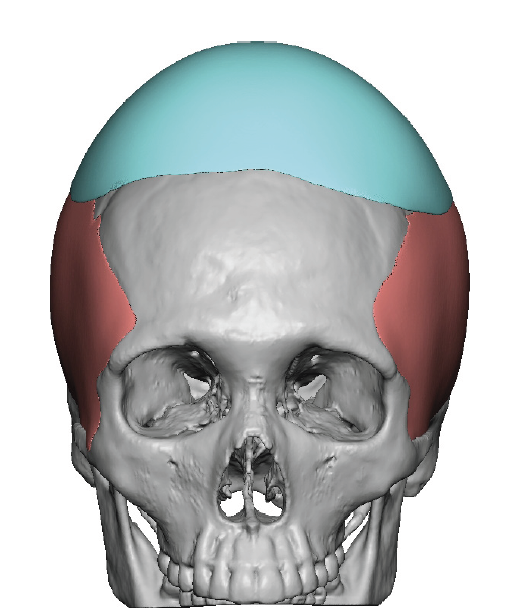

Desire for change of head shape from front view form an inverted V shape to a rounder and wider head shape.

Placement of custom extended forehead-temporal implants through incisions in the crease behind the ear. (he had a prior back of head skull implant which is green in the implant designs and which the head widening implants partially covered it)

Desire for change of head shape from front view form an inverted V shape to a rounder and wider head shape.

Placement of custom extended forehead-temporal implants through incisions in the crease behind the ear. (he had a prior back of head skull implant which is green in the implant designs and which the head widening implants partially covered it)